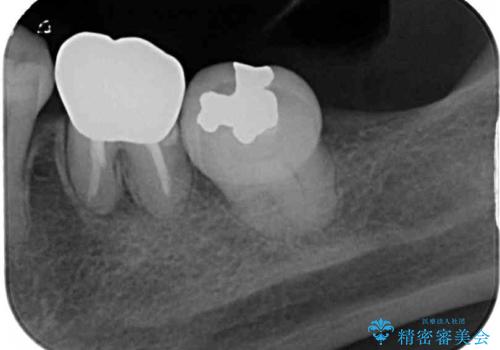

- 矯正治療後に、下顎奥歯の銀歯をすべてゴールドにすることを希望された患者様です。

セラミッククラウンやセラミックインレーによる補綴治療も提案しましたが、お友達にゴールドを自慢したいとのことで、ゴールドクラウンとゴールドインレーにて処置することとしました。